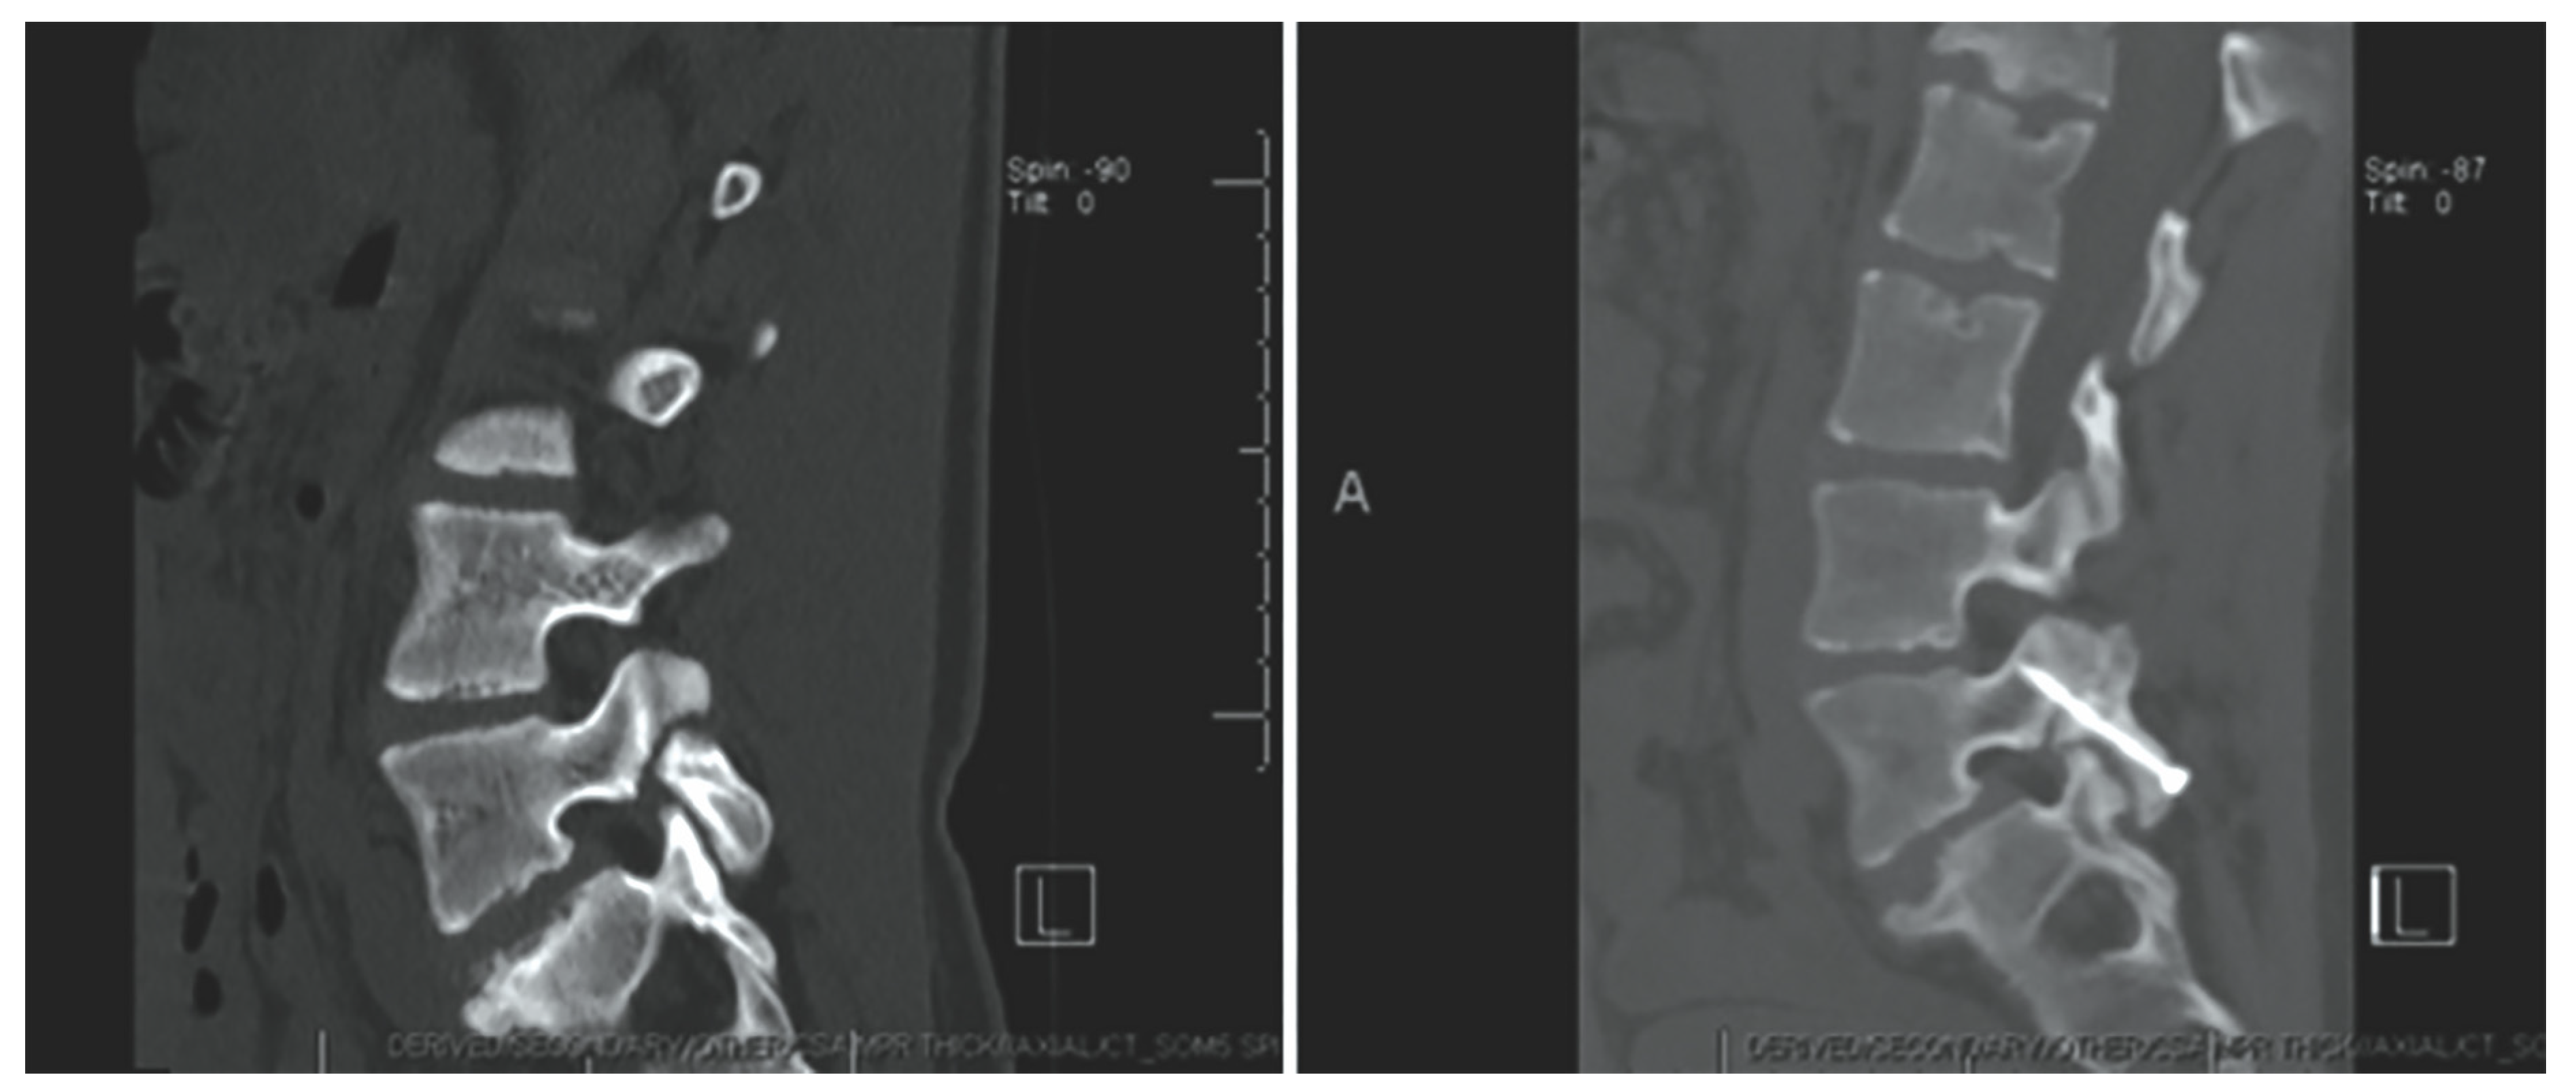

- Fayed, I.; Conte, A.G.; Voyadzis, J.-M. Success and failure of percutaneous minimally invasive direct pars repair: Analysis of fracture morphology. World Neurosurg. 2019, 126, 181–188. [Google Scholar] [CrossRef]

Levi Technique—Minimally Invasive Direct Pars Screw Placement

- Ghobrial, G.M.; Crandall, K.M.; Lau, A.; Williams, S.K.; Levi, A.D. Minimally invasive direct pars repair with cannulated screws and recombinant human bone morphogenetic protein: Case series and review of the literature. Neurosurg. Focus 2017, 43, E6. [Google Scholar] [CrossRef] [PubMed]